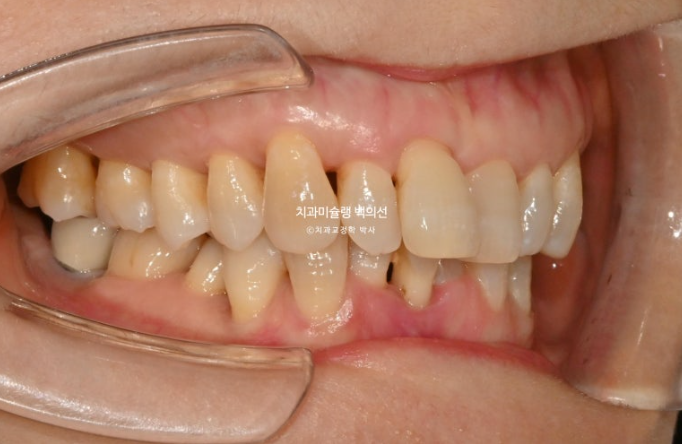

1년 전 치아 틀어짐이 점점 심해지면서 찾아오신 50대 환자분

예전에는 입이 편하게 다물어졌었는데 치아가 틀어지고 벌어지고 내려오면서 이제는 입이 편하게 안 다물어지는 것도 불편한 상태입니다.

위 앞니는 잇몸이 꽉 잡아주지를 못해서 점점 솟아 내려오고 튀어나오면서 치아사이가 벌어졌습니다.

작은어금니도 안으로 쓰러져 있어서 이 부분은 윗니와 엇갈려 물리는 가위교합 입니다.